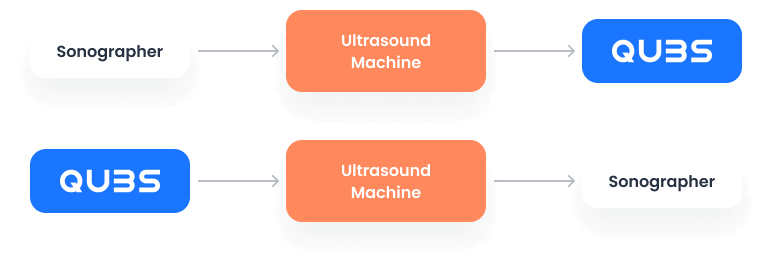

Experience a frictionless workflow even in remote settings. With QUBS, scan first without an internet connection; the platform intelligently creates patient and appointment details once connectivity is restored. Complete the addition of referrals, worksheets, and billings at your convenience, significantly reducing administrative tasks on the go, and focusing more on patient care during your mobile clinic operations.